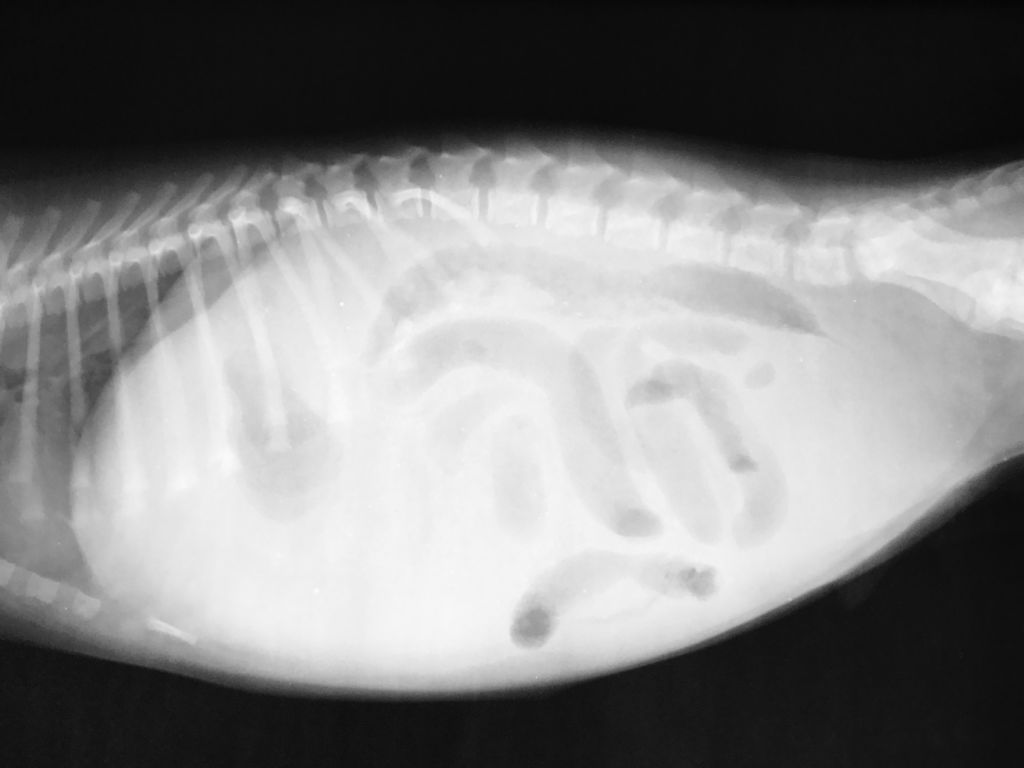

Для підтвердження діагнозу в клініці проводять діагностичний огляд, передбачає пальпацію, перкусію та аускультацію. Крім цього, обов’язково роблять прокол черевної стінки в області асциту з метою діагностики.

Проводять ультразвукове дослідження, рентген і беруть аналіз сечі.